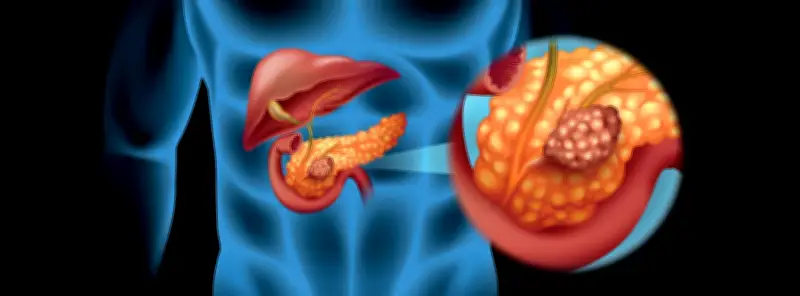

El equipo de Barbacid, quien también es jefe del Grupo de Oncología Experimental del Centro Nacional de Investigaciones Oncológicas (CNIO), había publicado en PNAS los resultados de un estudio que permitió eliminar en ratones el tipo más frecuente de cáncer de páncreas, el adenocarcinoma ductal, mediante una terapia combinada de tres fármacos. El tratamiento evitaba la aparición de resistencias y no mostraba efectos secundarios importantes en los modelos experimentales.

“Es importante destacar que esta terapia combinada fue bien tolerada. En resumen, estos resultados deberían guiar el desarrollo de nuevos ensayos clínicos que podrían beneficiar a los pacientes con adenocarcinoma ductal pancreático (PDAC)”, concluyó el estudio. Para presentar estos resultados, Barbacid dio una rueda de prensa en enero, donde también participaron las investigadoras principales, responsables de la Fundación CRIS contra el cáncer, y varios pacientes.